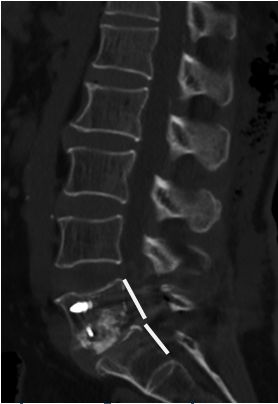

在完善了相关检查后刘阿姨被确诊为腰椎滑脱症—腰5椎体II度向前滑脱。

腰5椎体2度

向前滑脱

脊髓受压变形

由于刘阿姨的腰椎滑脱情况严重,曾经过一段时间的保守治疗却效果不佳,何升华主任决定采取手术方法复位滑脱椎体,解除神经压迫症状。